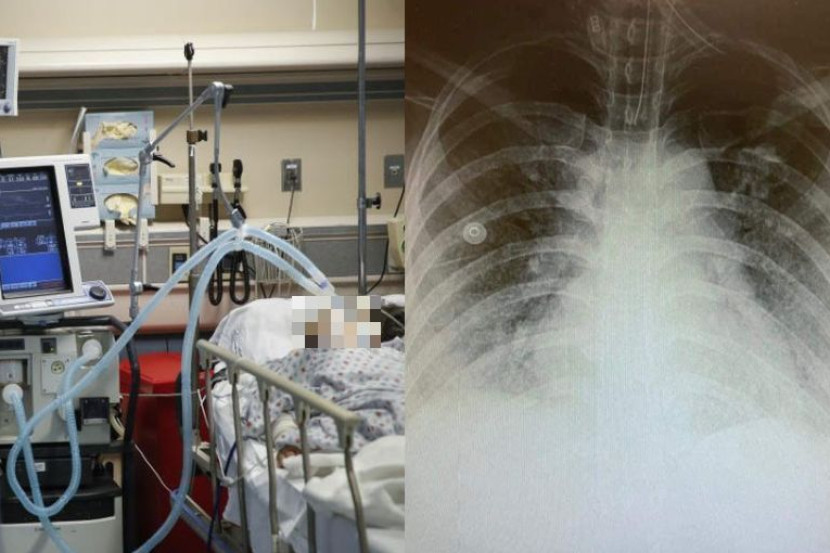

"X-ray paru-paru dan dada salah seorang pesakit kami di ICU Covid-19. Pesakit merupakan seorang bakal ibu berumur 20 tahun lebih yang sedang mengandung anak pertama.

"Dia merupakan seorang wanita yang sihat tanpa sebarang penyakit. Usia kandungan lebih kurang 35 minggu. Pesakit bekerja di sebuah pejabat dan tiada kontak dengan mana-mana pesakit Covid-19.

"Pada suatu malam yang dingin, pesakit tersebut datang ke sebuah hospital di Lembah Klang dengan gejala demam, batuk, sesak nafas dan kurang oksigen dalam darah.

"Pesakit kemudian segera dimasukkan ke ICU untuk rawatan lanjut dan ujian Covid-19 didapati positif," tulis doktor berkenaan.

Menurut doktor berkenaan, keadaan ibu muda itu makin melarat dan menjadi semakin kritikal, dengan mengalami kesesakan nafas yang teruk serta kadar oksigen dalam darahnya makin berkurang.

"Kemudian tiub pernafasan (intubation) dimasukkan dan dia bernafas menggunakan mesin bantuan pernafasan (ventilator) memandangkan oksigen dalam darahnya terlampau rendah.

Tambahnya, selepas pembedahan Caeserean Section, pesakit kembali dimasukkan ke wad ICU dalam keadaan yang pesakit masih ditidurkan (sedated) dan bernafas menggunakan mesin bantuan pernafasan (ventilator).